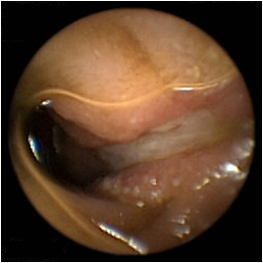

④胶囊内镜

胶囊内镜检查过程

胶囊内镜检查只需三个简单的步骤 , 即可完成检查:吞服胶囊,拍摄记录,回放观察。

胶囊内镜通过采集、储存、回放全小肠粘膜彩色图像,能够直接观察全小肠粘膜,敏感性高,是目前唯—的无 创、可视的全小肠检查手段。适用于各个年龄层次的患者,尤其是合并心、肺、脑、肾等 多 脏器疾病的患者,以及难以耐受内镜及其他有创检查的老年患者。